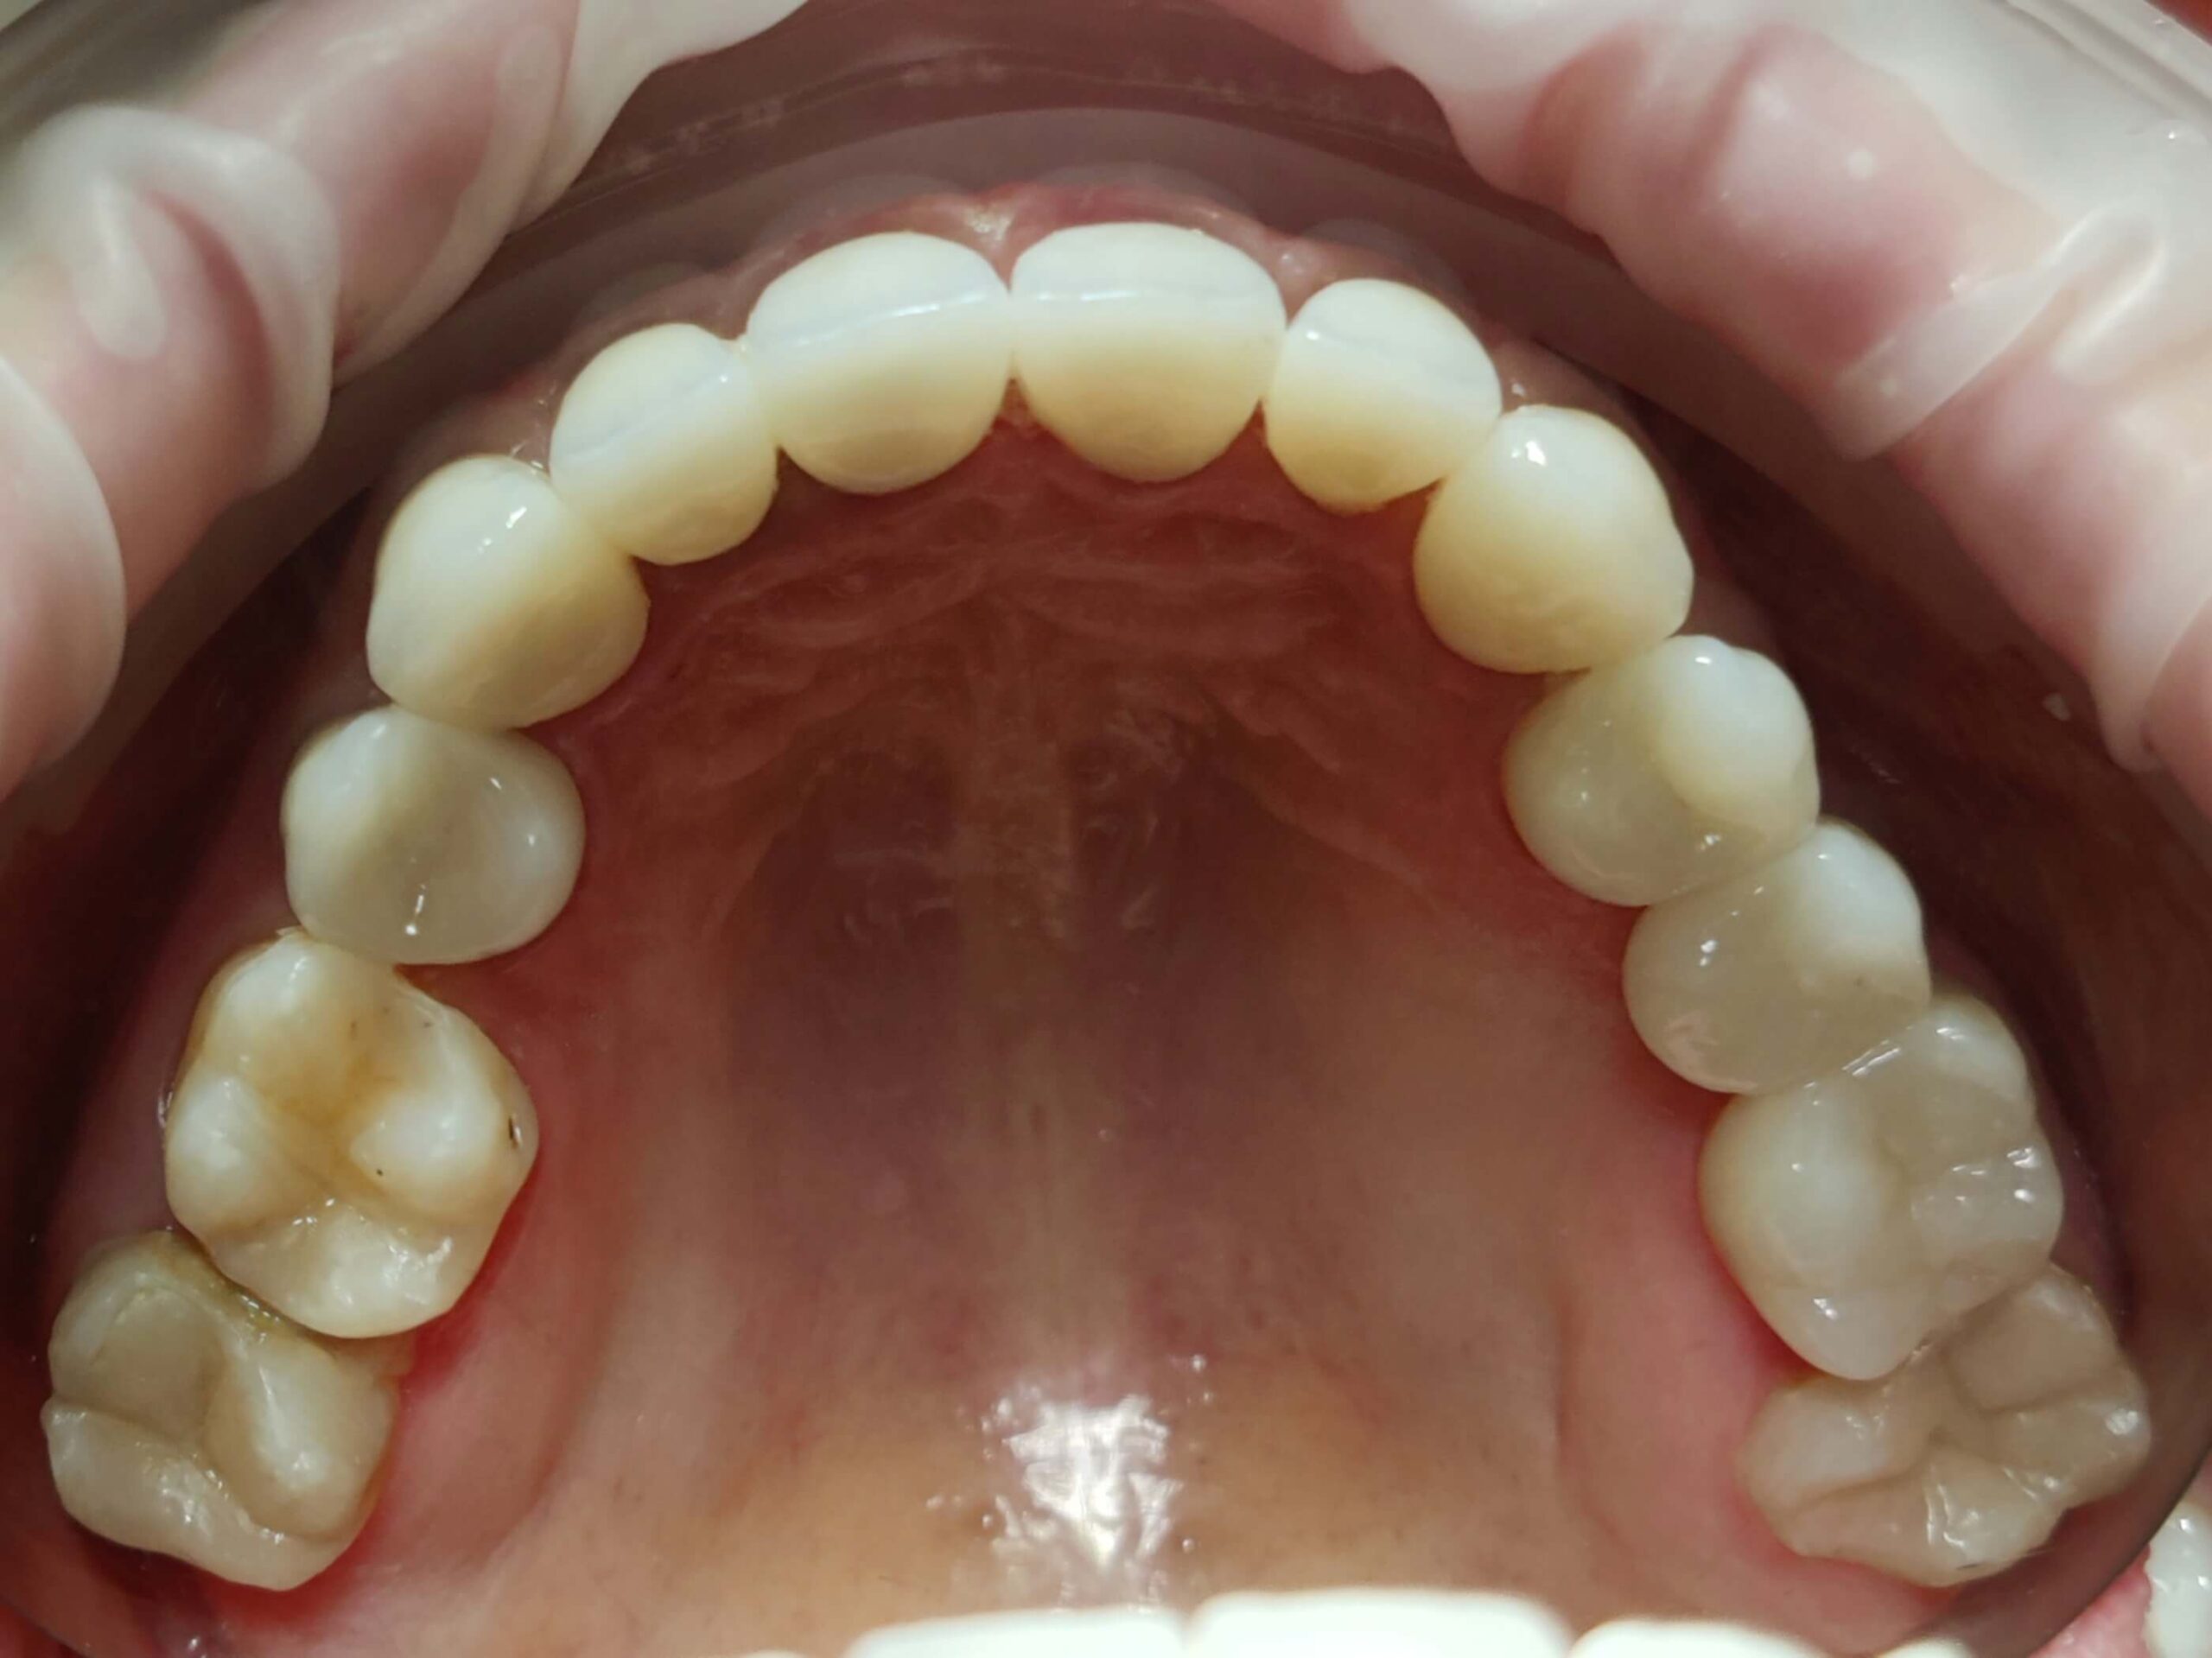

Протезування коронками верхньої щелепи

Вихідна ситуація: скарги пацієнта на часткову відсутність зубів на верхній та нижній щелепах, незадовільна форма зубів верхньої щелепи. Після детального огляду було прийняте рішення про відновлення зубного ряду за допомогою коронок на верхній щелепі.

Категорія: Імплантологія